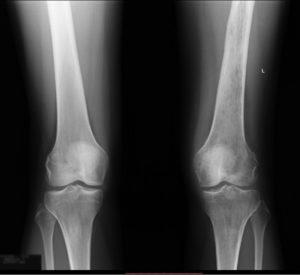

Лечение менисцита коленного сустава врач назначает после тщательного обследования и анализа полученных данных. В качестве первой помощи рекомендуется обеспечить покой травмированной ноги, приложить холод и зафиксировать колено с помощью эластичного бинта.

Операция назначается пациентам при разрыве мениска, особенно если после консервативного лечения не наблюдается улучшений. Хирургическое вмешательство направлено на сохранение мениска и восстановление его нормальной работы.

В ходе процедуры врачи удаляют поврежденную часть хряща. Применяется артроскопический метод. Специалисты создают небольшой разрез в суставе, через который вводят хирургические инструменты и видеокамеру. Она позволяет наблюдать за процессом внутри сустава в реальном времени.